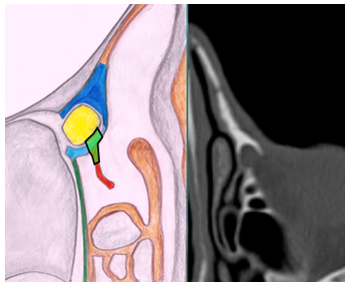

E-DCR Type 1(UP in retro-lacrimal position) (Figure 3a): in this case the transillumination with the light probe shows the projection of the lacrimal sac on the lateral nasal wall in front of the UP. The lacrimal bone is skeletonized with a diamond burr, without creating a mucosal flap to expose it, and then the lacrimal sac is identified and marsupialized.

Figure 3a UP in retro-lacrimal position.